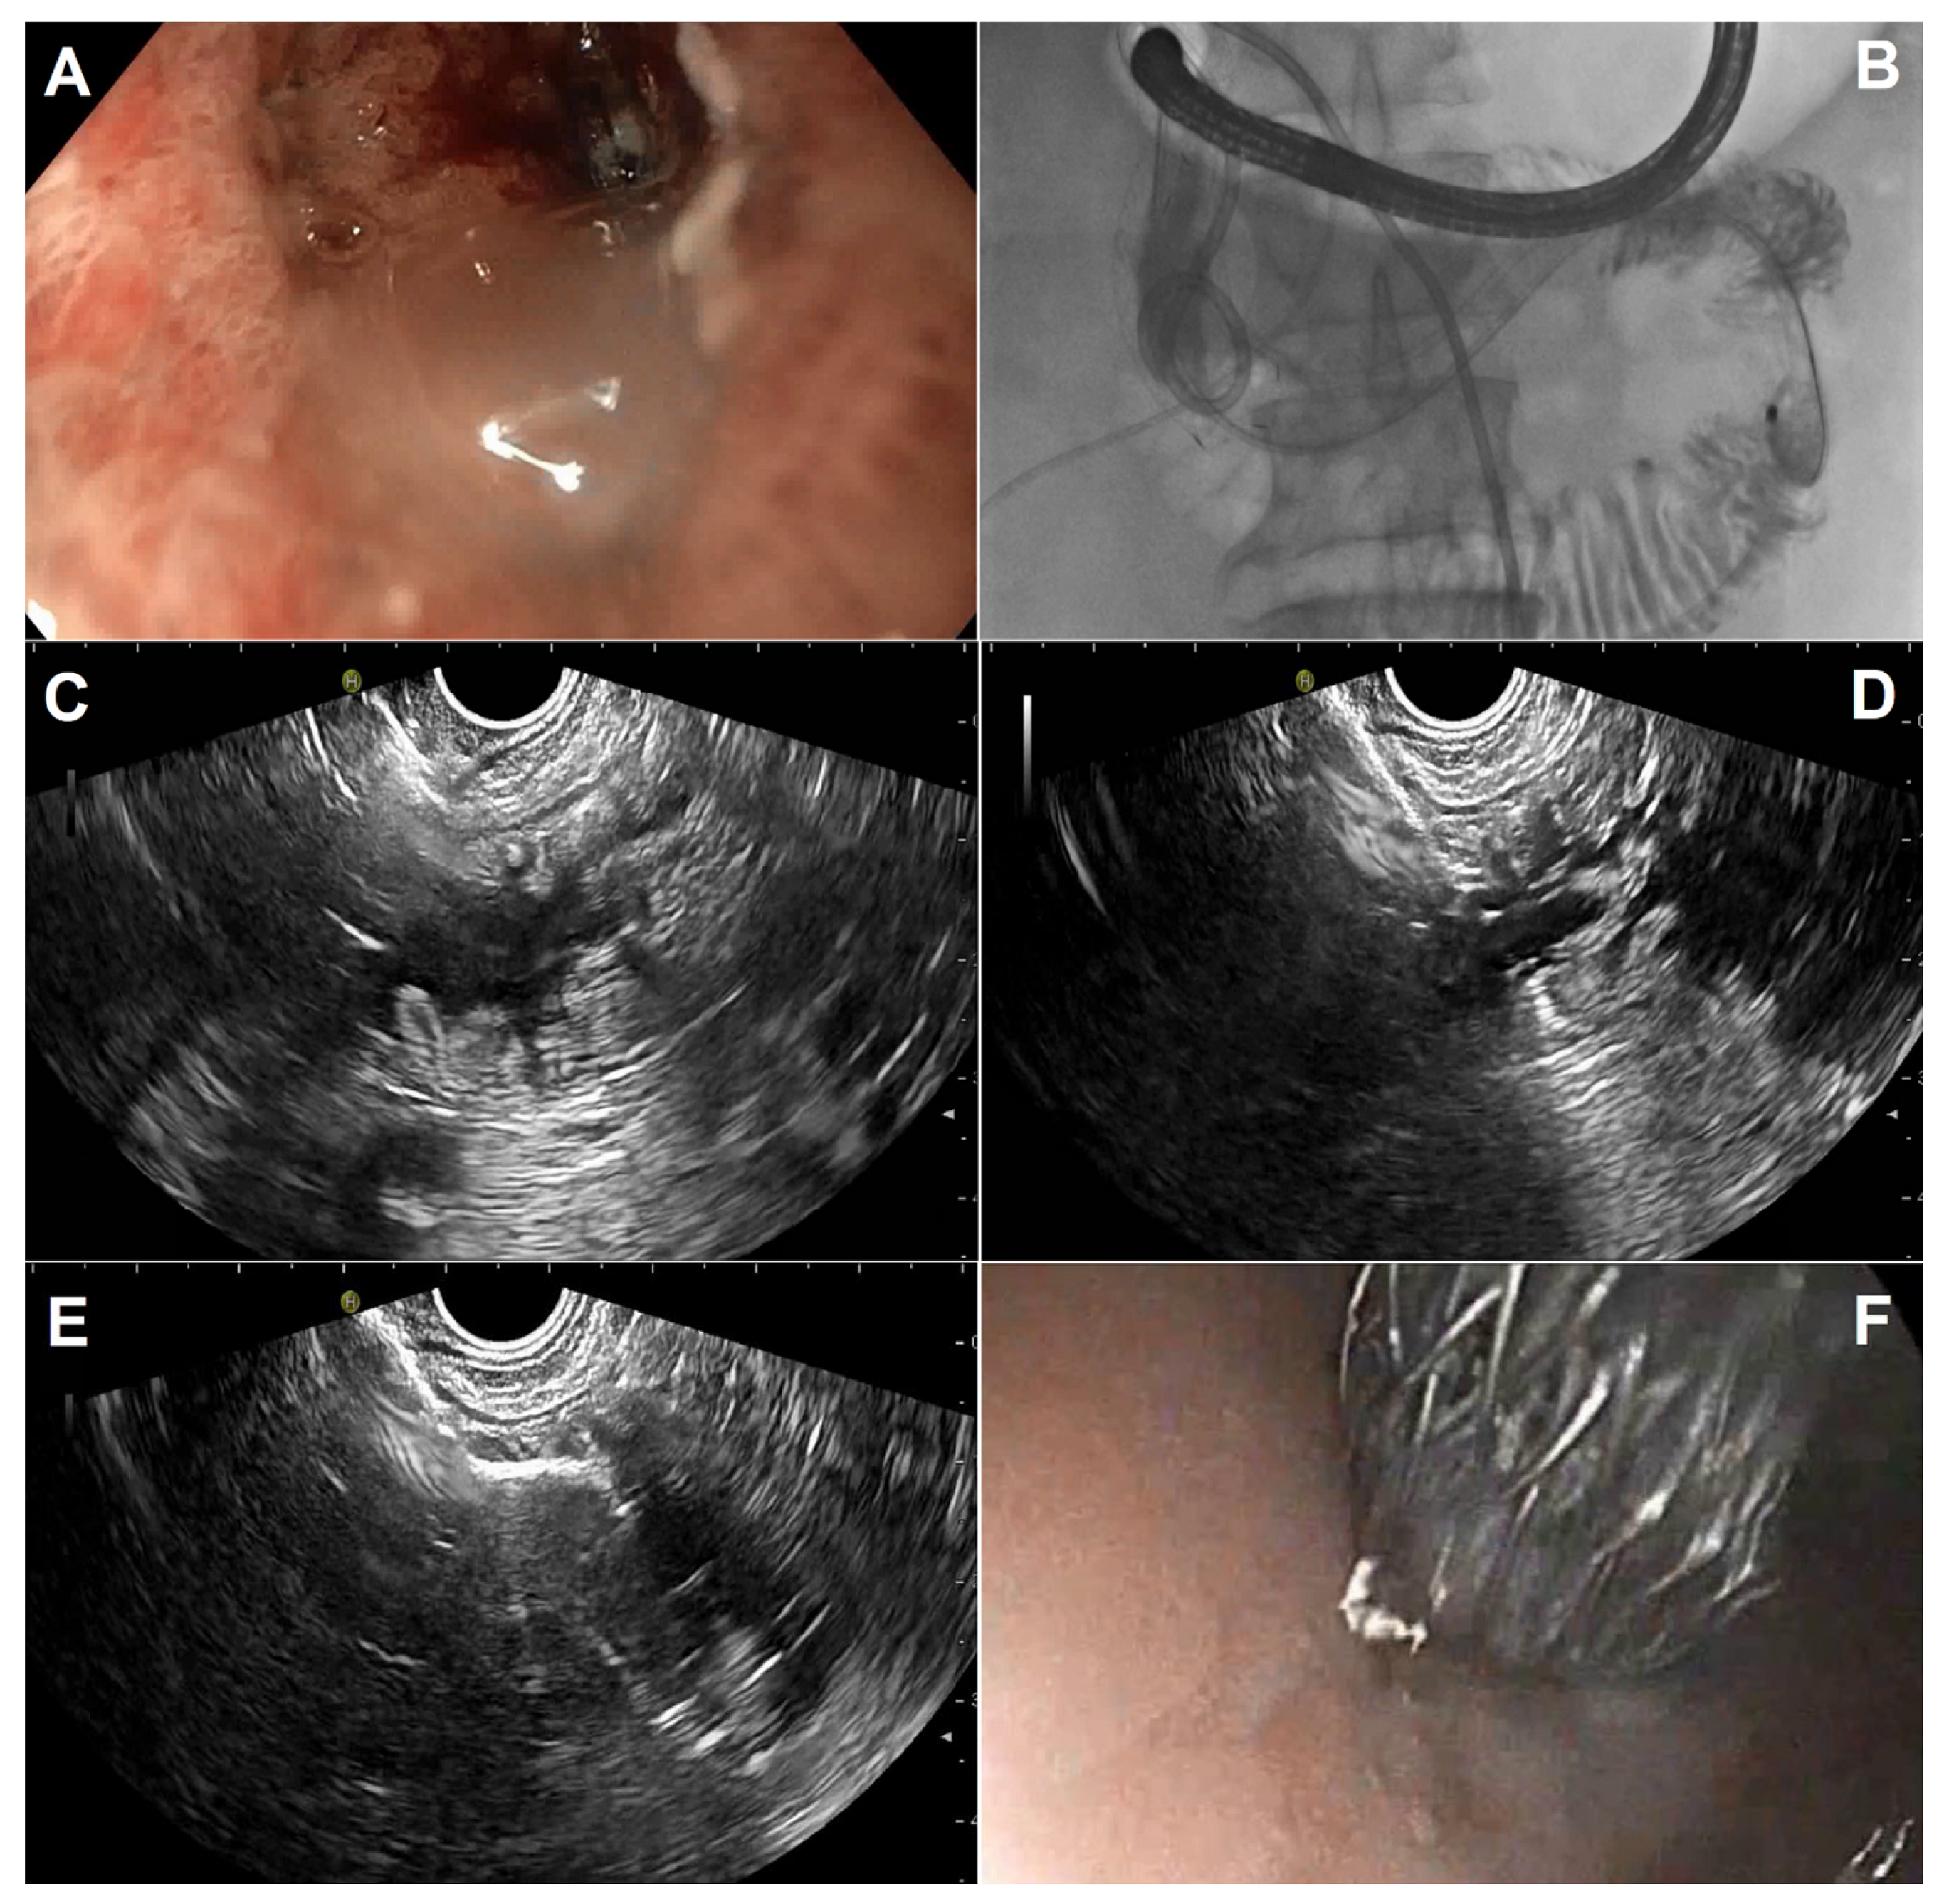

Figure 2.

EUS-guided gastroenterostomy in a patient with duodenal stenosis from invasive pancreatic cancer previously treated by duodenal stenting using the WEST technique: (A) endoscopic image of a duodenal stent with tumoral ingrowth; (B) radiologic image depicting a 7 Fr nasobiliary catheter placed through the stricture after guidewire placement, through which saline and contrast are infused; (C) EUS identification of the jejunal target loop using fluid cavitation and identification of the nasobiliary catheter; (D) free-hand intrajejunal access with the electrocautery device (100 W, effect 5); (E) intrajejunal distal flange deployment under EUS guidance; (F) intragastric proximal flange deployment under endoscopic control.